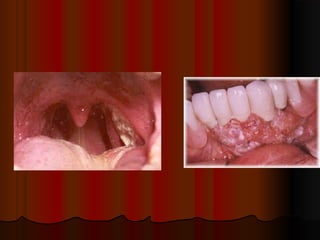

มะเร็งในช่องปากและคอ

 FindIt Early and Be Cured

 Here's What You Should Watch for:

A lump in the neck

Change in the voice

Bringing up blood

Swallowing problems

high risk of head and neck

 Identifying

Cancer :tobacco user 90%

Head and neck cancer

Hoarseness

Thyroid cancer

Treatment of cancer

Surgery

Radiation

Early detection is the best way